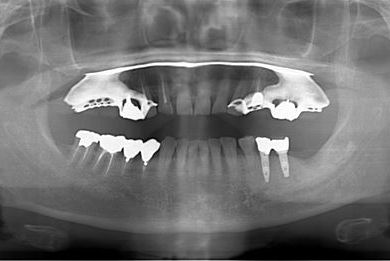

抜歯即日スピードインプラント治療+歯周外科治療

| 性別/年齢 | 男性 / 62歳 | ||||||||||||||||||||||||||||||||

| 主訴 | 左下の奥歯のブリッジがゆれて、痛みがある。 | ||||||||||||||||||||||||||||||||

| 治療方針 | 抜歯と同時にインプラント埋入を行い、治療期間を短縮する。 | ||||||||||||||||||||||||||||||||

| 治療内容 | インプラント2本(抜歯即日スピードインプラント)、ハイブリッドセラミッククラウン2本、歯周外科治療 | ||||||||||||||||||||||||||||||||